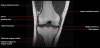

무릎 관절의 MRI 단면영상2016-08-31카테고리 106원본 보기1. Sagittal section 2. Coronal section 3. Axial section ← 이전 글전방 족근관증후군(Anterior tarsal tunnel syndrome) : 발등이 꽉 끼는 구두를 신은 후부터 발등을 누르면 아프고 엄지와 검지 발가락 사이가 저려요다음 글 →흉곽출구증후군(Thoracic outlet syndrome) : 팔이 아프고 감각이 떨어지면서 저려요같은 카테고리 글2017-06-10톰슨 검사(Thompson test) : 아킬레스건 파열을 조사하는 테스트2017-06-09Apley 압박 검사(Apley compression test) : 반월상 연골 손상을 조사하는 테스트2017-06-08맥머레이 시험(McMurray test) : 반월상 연골 손상을 조사하는 테스트← 전체 글로 돌아가기